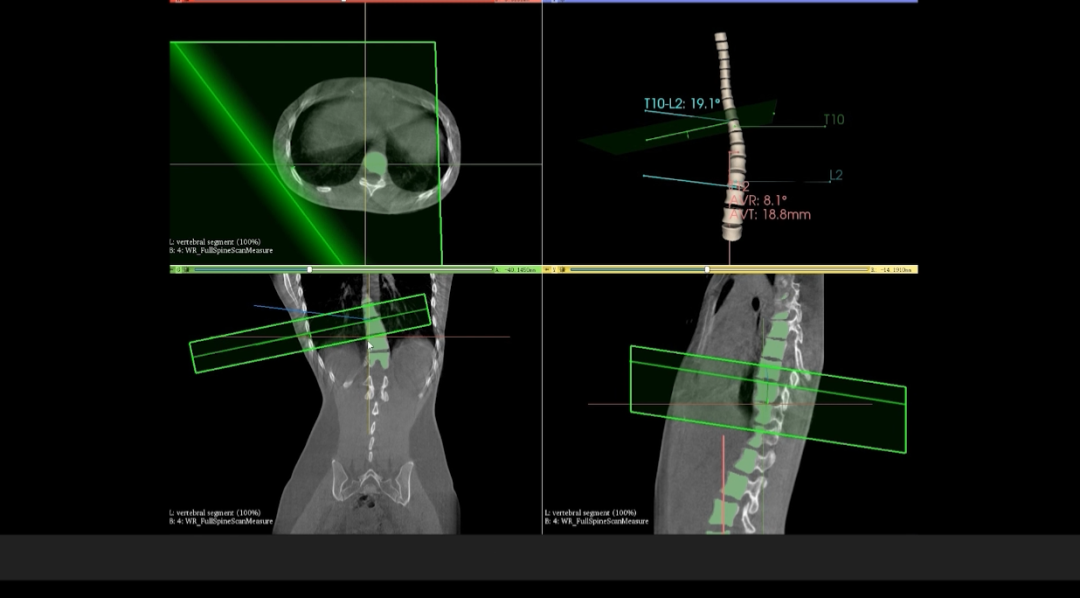

WR-3D它是一種基于CBCT的掃描方式并且能完成負(fù)重位狀態(tài)下部位三維掃描與重建的全新技術(shù),可支持三維影像掃描信息實(shí)時同步處理;值得一提的是,該技術(shù)完全基于數(shù)字化X線設(shè)備平臺打造,劑量輻射水平遠(yuǎn)低于CT,同時也將原本DR的圖像由二維擴(kuò)展到三維,獲得橫斷、矢狀、冠狀多方位圖像。在臨床診斷以及醫(yī)療方案制定中具有極大的價值意義。相較于普通平片下的負(fù)重位掃描,CBCT-DR能夠避免二維狀態(tài)下的組織結(jié)構(gòu)重疊、密度分辨率不足、組織解剖結(jié)構(gòu)難以分辨等問題,能全面地呈現(xiàn)被檢查部位在多個角度下的三維影像信息,極大地降低了二維負(fù)重位檢查帶來的漏診率。

在與華西醫(yī)院開展的技術(shù)合作中,WR-3D的立位脊柱三維攝影技術(shù)能提供更加豐富的臨床信息,通過WR-3D的三維全脊柱掃描與重建,即可完成脊柱三維影像重建,無需進(jìn)行角度拼接,消除二維Cobb角度測量的誤差,可以實(shí)現(xiàn)包括Cobb角、前/后凸角、椎體偏移/旋轉(zhuǎn)向量圖、椎體旋轉(zhuǎn)角條形圖、矢/冠狀面垂直軸偏距數(shù)據(jù)的自動測量;這項技術(shù)將為脊柱矯形的臨床診斷帶來從定性到定量的轉(zhuǎn)變,提供豐富的數(shù)據(jù)和圖表,為臨床尤其是手術(shù)方案的規(guī)劃制定提供非常精準(zhǔn)的定量化數(shù)據(jù)支撐,不僅可以對脊柱冠狀面參數(shù)進(jìn)行精準(zhǔn)的定量評估,還可對矢狀面包括,頸椎前凸、后凸、腰椎前凸和后凸進(jìn)行非常精準(zhǔn)的評估。